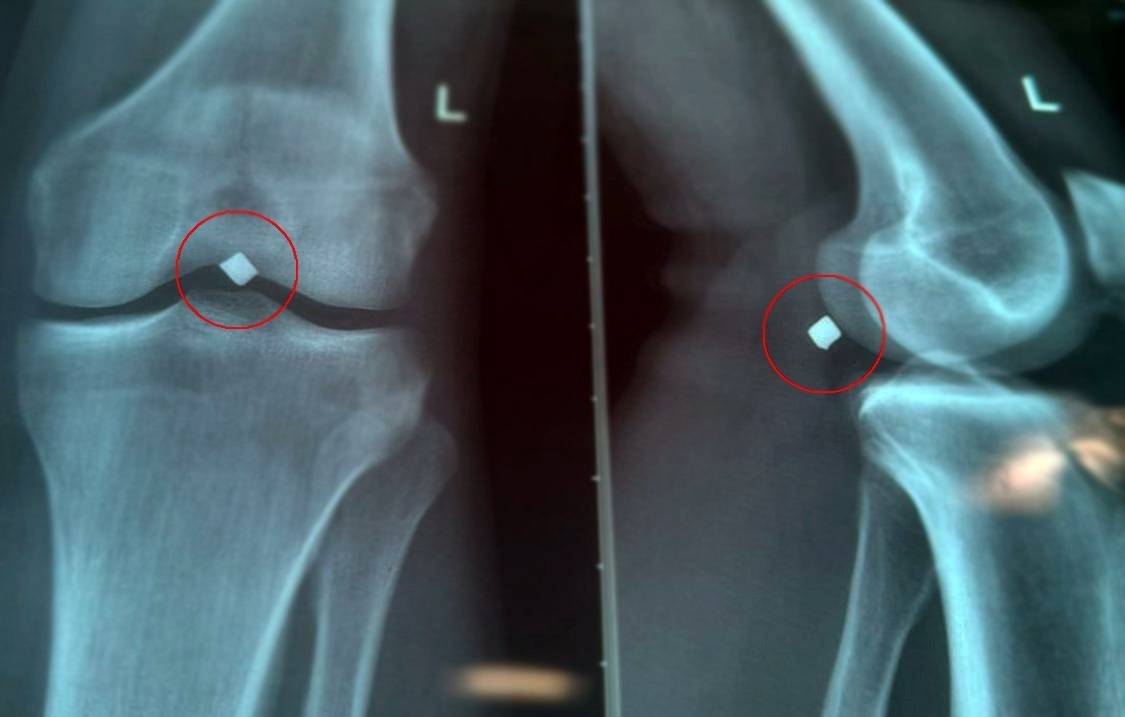

«Провели обследование, рентген показал местонахождение осколка. Во время вмешательства выяснилось, что осколок лежал прямо на стенке подколенной вены и практически пролабировал ее, создавая прямую угрозу жизнеугрожающего кровотечения. Работа хирургов требовала ювелирной точности. Операция прошла успешно, осколок был благополучно и аккуратно удален», — рассказал к.м.н., врач сердечно-сосудистый хирург Карпов Вячеслав Владимирович.